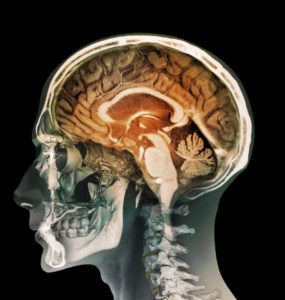

علم الصحة هو مجموعة في التخصصات في العلوم التطبيقية التي تتعامل مع الصحة.

تنقسم علوم الصحة إلى قسمين : دراسة جسم الإنسان والبحث لتعزيز معرفتنا بالآليات التي يعمل بها الجسم الحي وممرضاته وعلم الصحة التطبيقي الذي يهتم بتطبيق هذه المعرفة لتحسين الصحة، ومعالجة وشفاء الأمراض، وفهم كيفية عمل وظائف الحيوانات والإنسان.